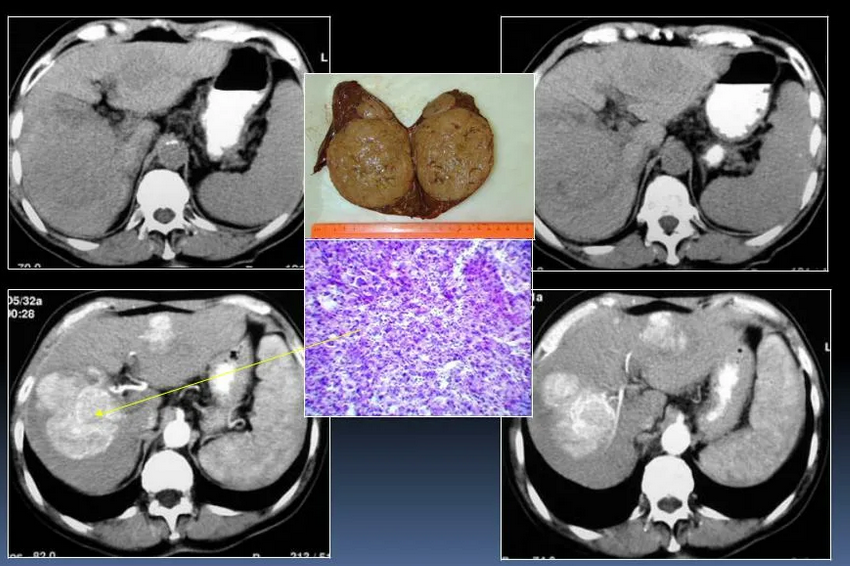

Множественные mts печени

Множественные mts печени 118 фотографий